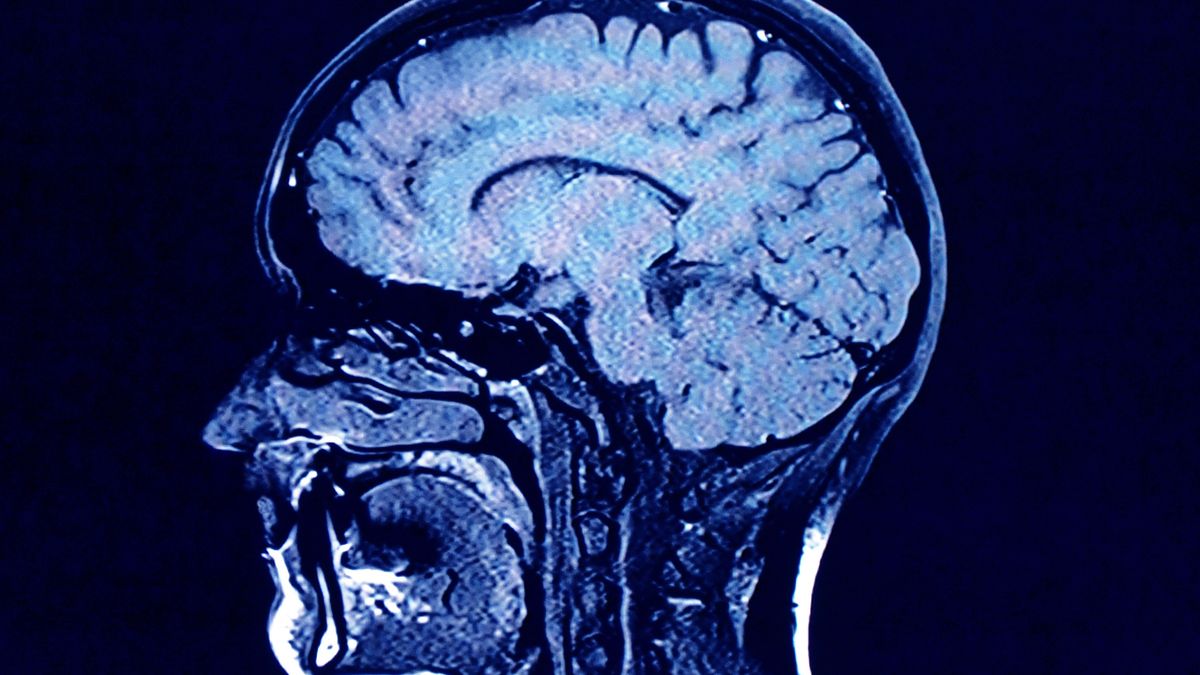

Lekarze, którzy badają ozdrowieńców, mówią o tzw. mgle mózgowej.

Naukowcy nie są pewni, co powoduje mgłę mózgową, która różnie się objawia i dotyka nawet tych, którzy podczas walki z koronawirusem nie mieli chorób współistniejących. Przyczyny tej dolegliwości są na razie tajemnicą, częściowo również dlatego, że objawy są tak różnorodne.

Badania nad mgłą mózgową, na którą cierpią pacjenci po koronawirusie, trwają.